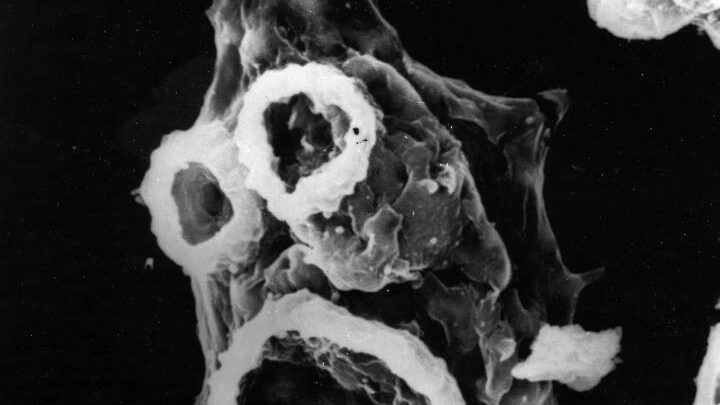

La Naegleria fowleri, que causa la meningoencefalitis amebiana primaria, es un parásito típico de aguas dulces templadas y estancadas, y la alberca en que se “contagió” la menor cumplía con todos “los niveles de cloro y temperatura considerados seguros”.